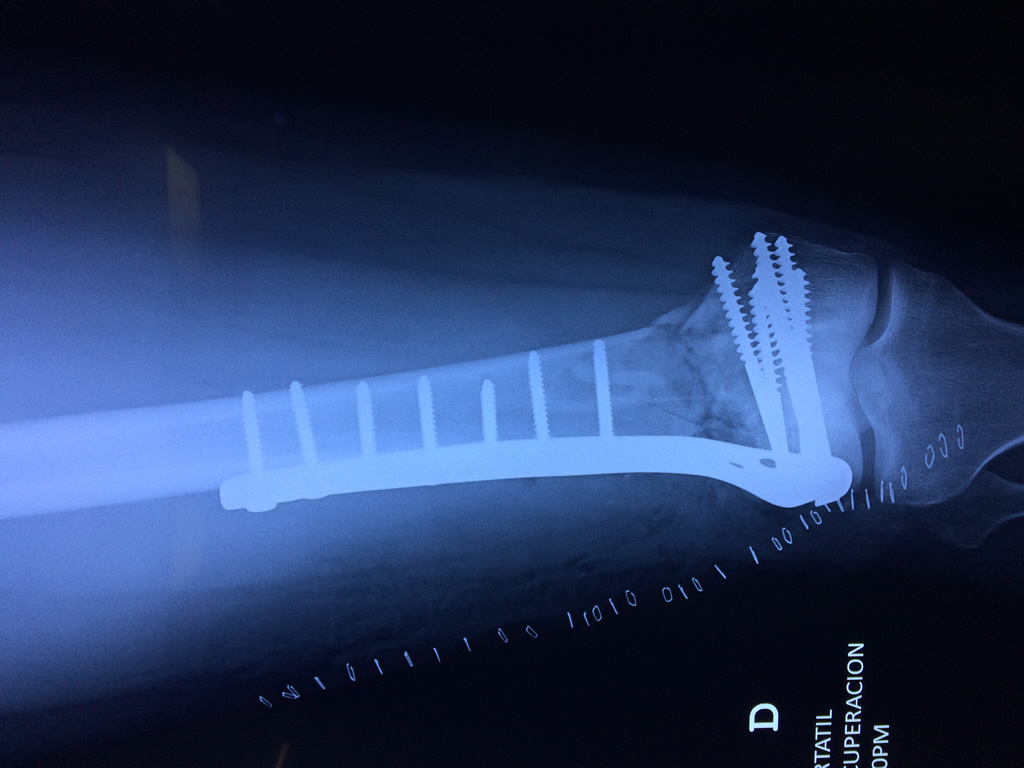

Cirugias en El Salvador - Fémur

El fémur es el hueso del muslo, el segundo segmento del miembro inferior. Es el hueso más largo, fuerte y voluminoso del cuerpo humano.